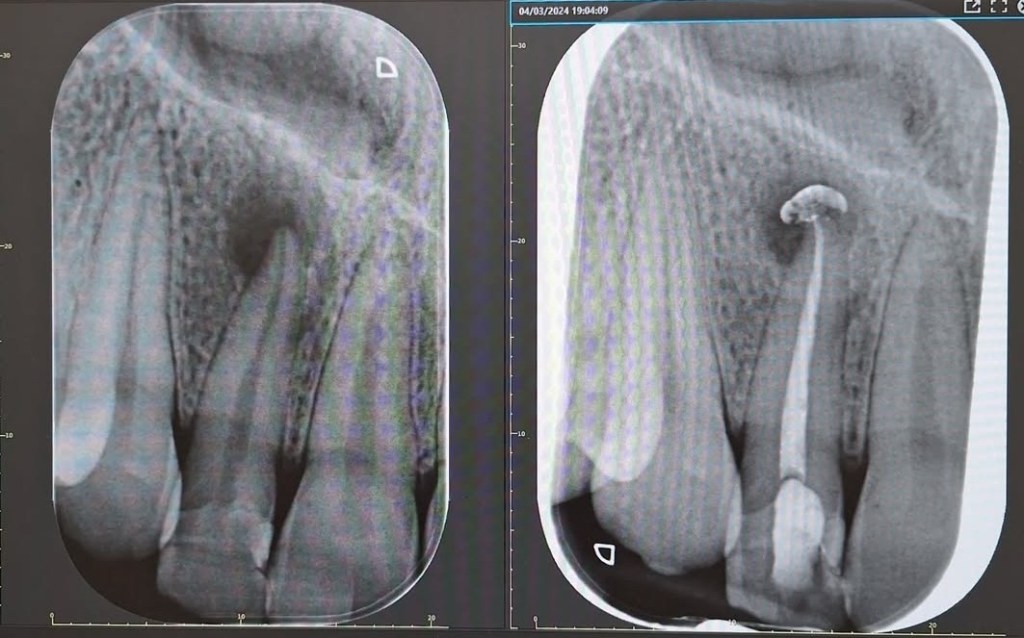

- chiusura dei canali, sigillati tramite una gomma termoplastica

- controllo radiografico